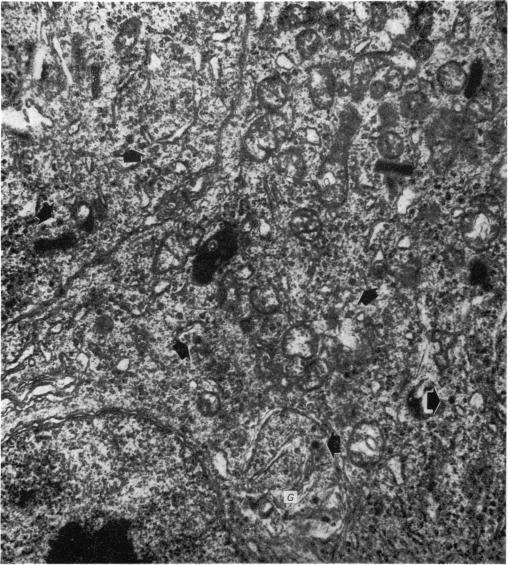

The pineal gland of chicks treated with oestrogens and androgens has been studied histochemically and ultrastructurally from post-hatching until 90 days of age. The results obtained may demonstrate a precocious maturity of the gland caused by its response to the early high level of sex hormones circulating in the blood.

对用雌激素和雄激素处理过的雏鸡的松果体进行了组织化学和超微结构研究,研究从雏鸡孵化后直至90日龄。所获得的结果可能表明,由于松果体对血液中早期高水平性激素的反应,该腺体出现早熟。